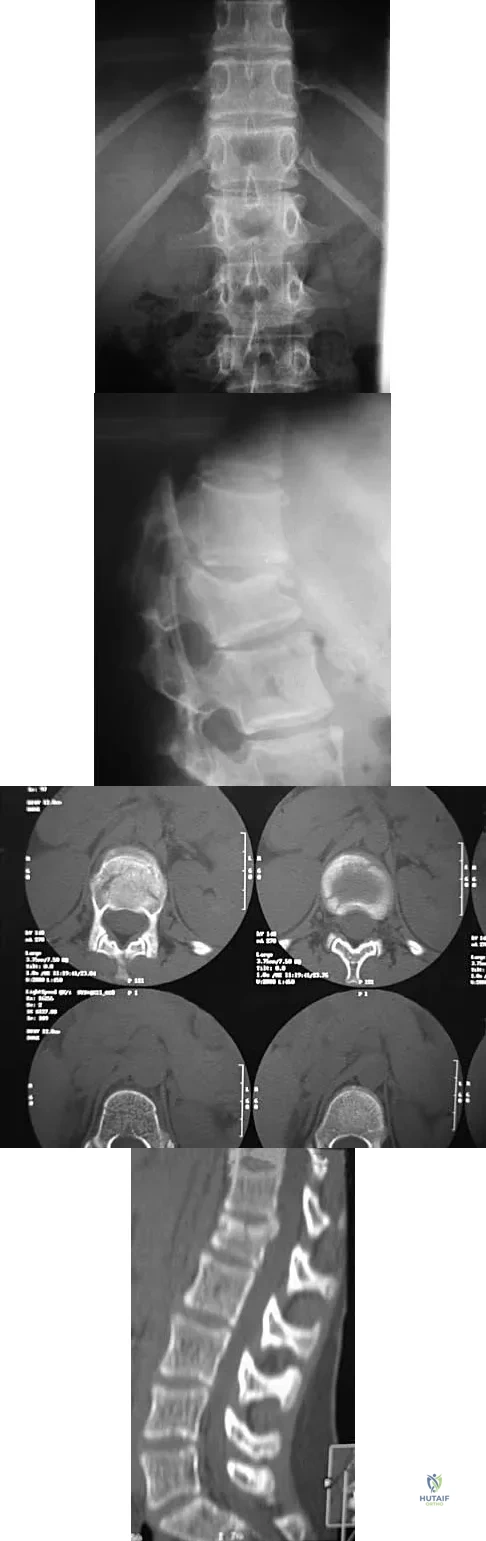

A skeletally mature 15-year-old girl who was thrown from the car in a rollover accident sustained the injuries shown in Figures 23a through 23d. Examination reveals no neurologic deficit, but the patient has moderate posterior spinal tenderness at the level of the injury. What is the most appropriate treatment?

Explanation